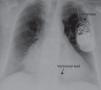

A 74-year-old woman with hypertension, dyslipidemia, and obesity as cardiovascular risk factors was diagnosed with nonobstructive hypertrophic cardiomyopathy with preserved systolic function. During follow-up, she presented sustained syncopal monomorphic ventricular tachycardias and a dual-chamber cardioverter-defibrillator was accordingly implanted; both leads used passive fixation (Figure 1).